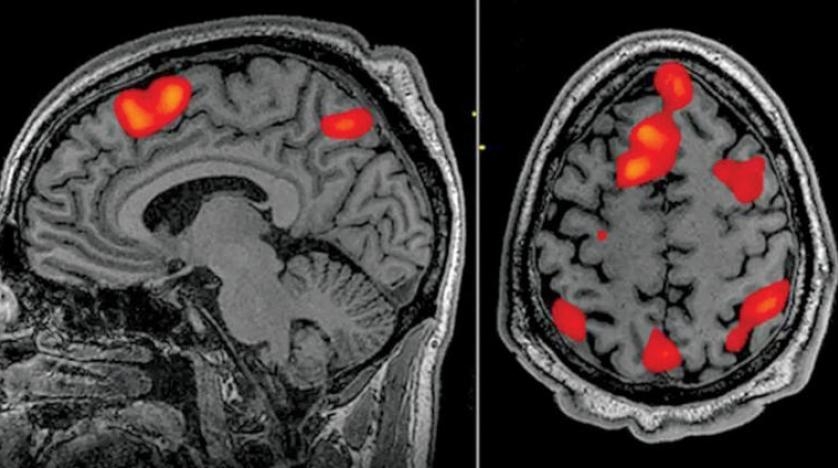

طُوّر جهاز فك ترميز يعتمد على الذكاء الصناعي، قادر على ترجمة نشاط الدماغ إلى نص متدفق باستمرار، في اختراق يتيح قراءة أفكار المرء بطريقة غير جراحية، وذلك للمرة الأولى على الإطلاق، حسب صحيفة «الغارديان» البريطانية.

وبمقدور جهاز فك الترميز إعادة بناء الكلام بمستوى هائل من الدقة، أثناء استماع الأشخاص لقصة ما - أو حتى تخيلها في صمت - وذلك بالاعتماد فقط على مسح البيانات بالتصوير بالرنين المغناطيسي الوظيفي فقط.

ويذكر أنه من المثير في هذا الإنجاز أنه يتغلب على قيود أساسية مرتبطة بالتصوير بالرنين المغناطيسي الوظيفي، وترتبط بحقيقة أنه بينما يمكن لهذه التكنولوجيا تعيين نشاط الدماغ إلى موقع معين بدقة عالية على نحو مذهل، يبقى هناك تأخير زمني كجزء أصيل من العملية، ما يجعل تتبع النشاط في الوقت الفعلي في حكم المستحيل.

ويقع هذا التأخير لأن فحوصات التصوير بالرنين المغناطيسي الوظيفي تقيس استجابة تدفق الدم لنشاط الدماغ، والتي تبلغ ذروتها وتعود إلى خط الأساس خلال قرابة 10 ثوانٍ، الأمر الذي يعني أنه حتى أقوى جهاز فحص لا يمكنه تقديم أداء أفضل من ذلك.